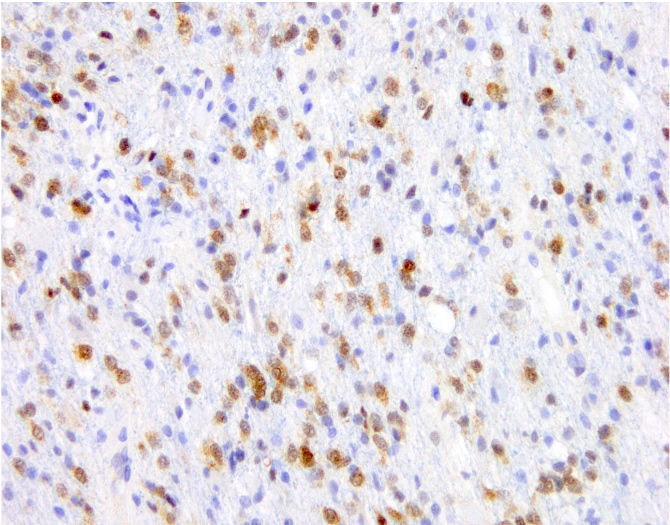

Positive stains

- IDH1 (R132H)

- Positive in > 90% of oligodendrogliomas (Acta Neuropathol 2009;118:599)

- Negative staining is not incompatible with oligodendroglioma if 1p / 19q codeletion is present

- Olig2, GFAP

- ATRX (retained; wildtype pattern)

- p53 (weak staining in rare cells; wildtype staining pattern)

- Ki67:

- Grade 2 tumors: usually < 5% of tumor nuclei

- Grade 3 tumors: generally > 10% of tumor nuclei (Neuro Oncol 2014;16:1244, Neuro Oncol 2016;18:888)

- Trio of IDH1 (R132H), ATRX and p53 is useful to distinguish oligodendroglioma from IDH mutant astrocytoma (Acta Neuropathol 2012;124:615)